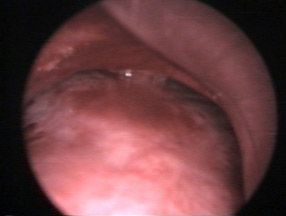

Ces ponctions peuvent être réalisées grâce au

guidage du scanner ou sous échographie endo-bronchique (photo 1). Le ganglion

fait ici mois de 10 mm de diamètre . il est au contact de l'artère pulmonaire

et pourtant il peut être ponctionné en toute sécurité grâce au guidage

échographique de l’écho-endoscope.